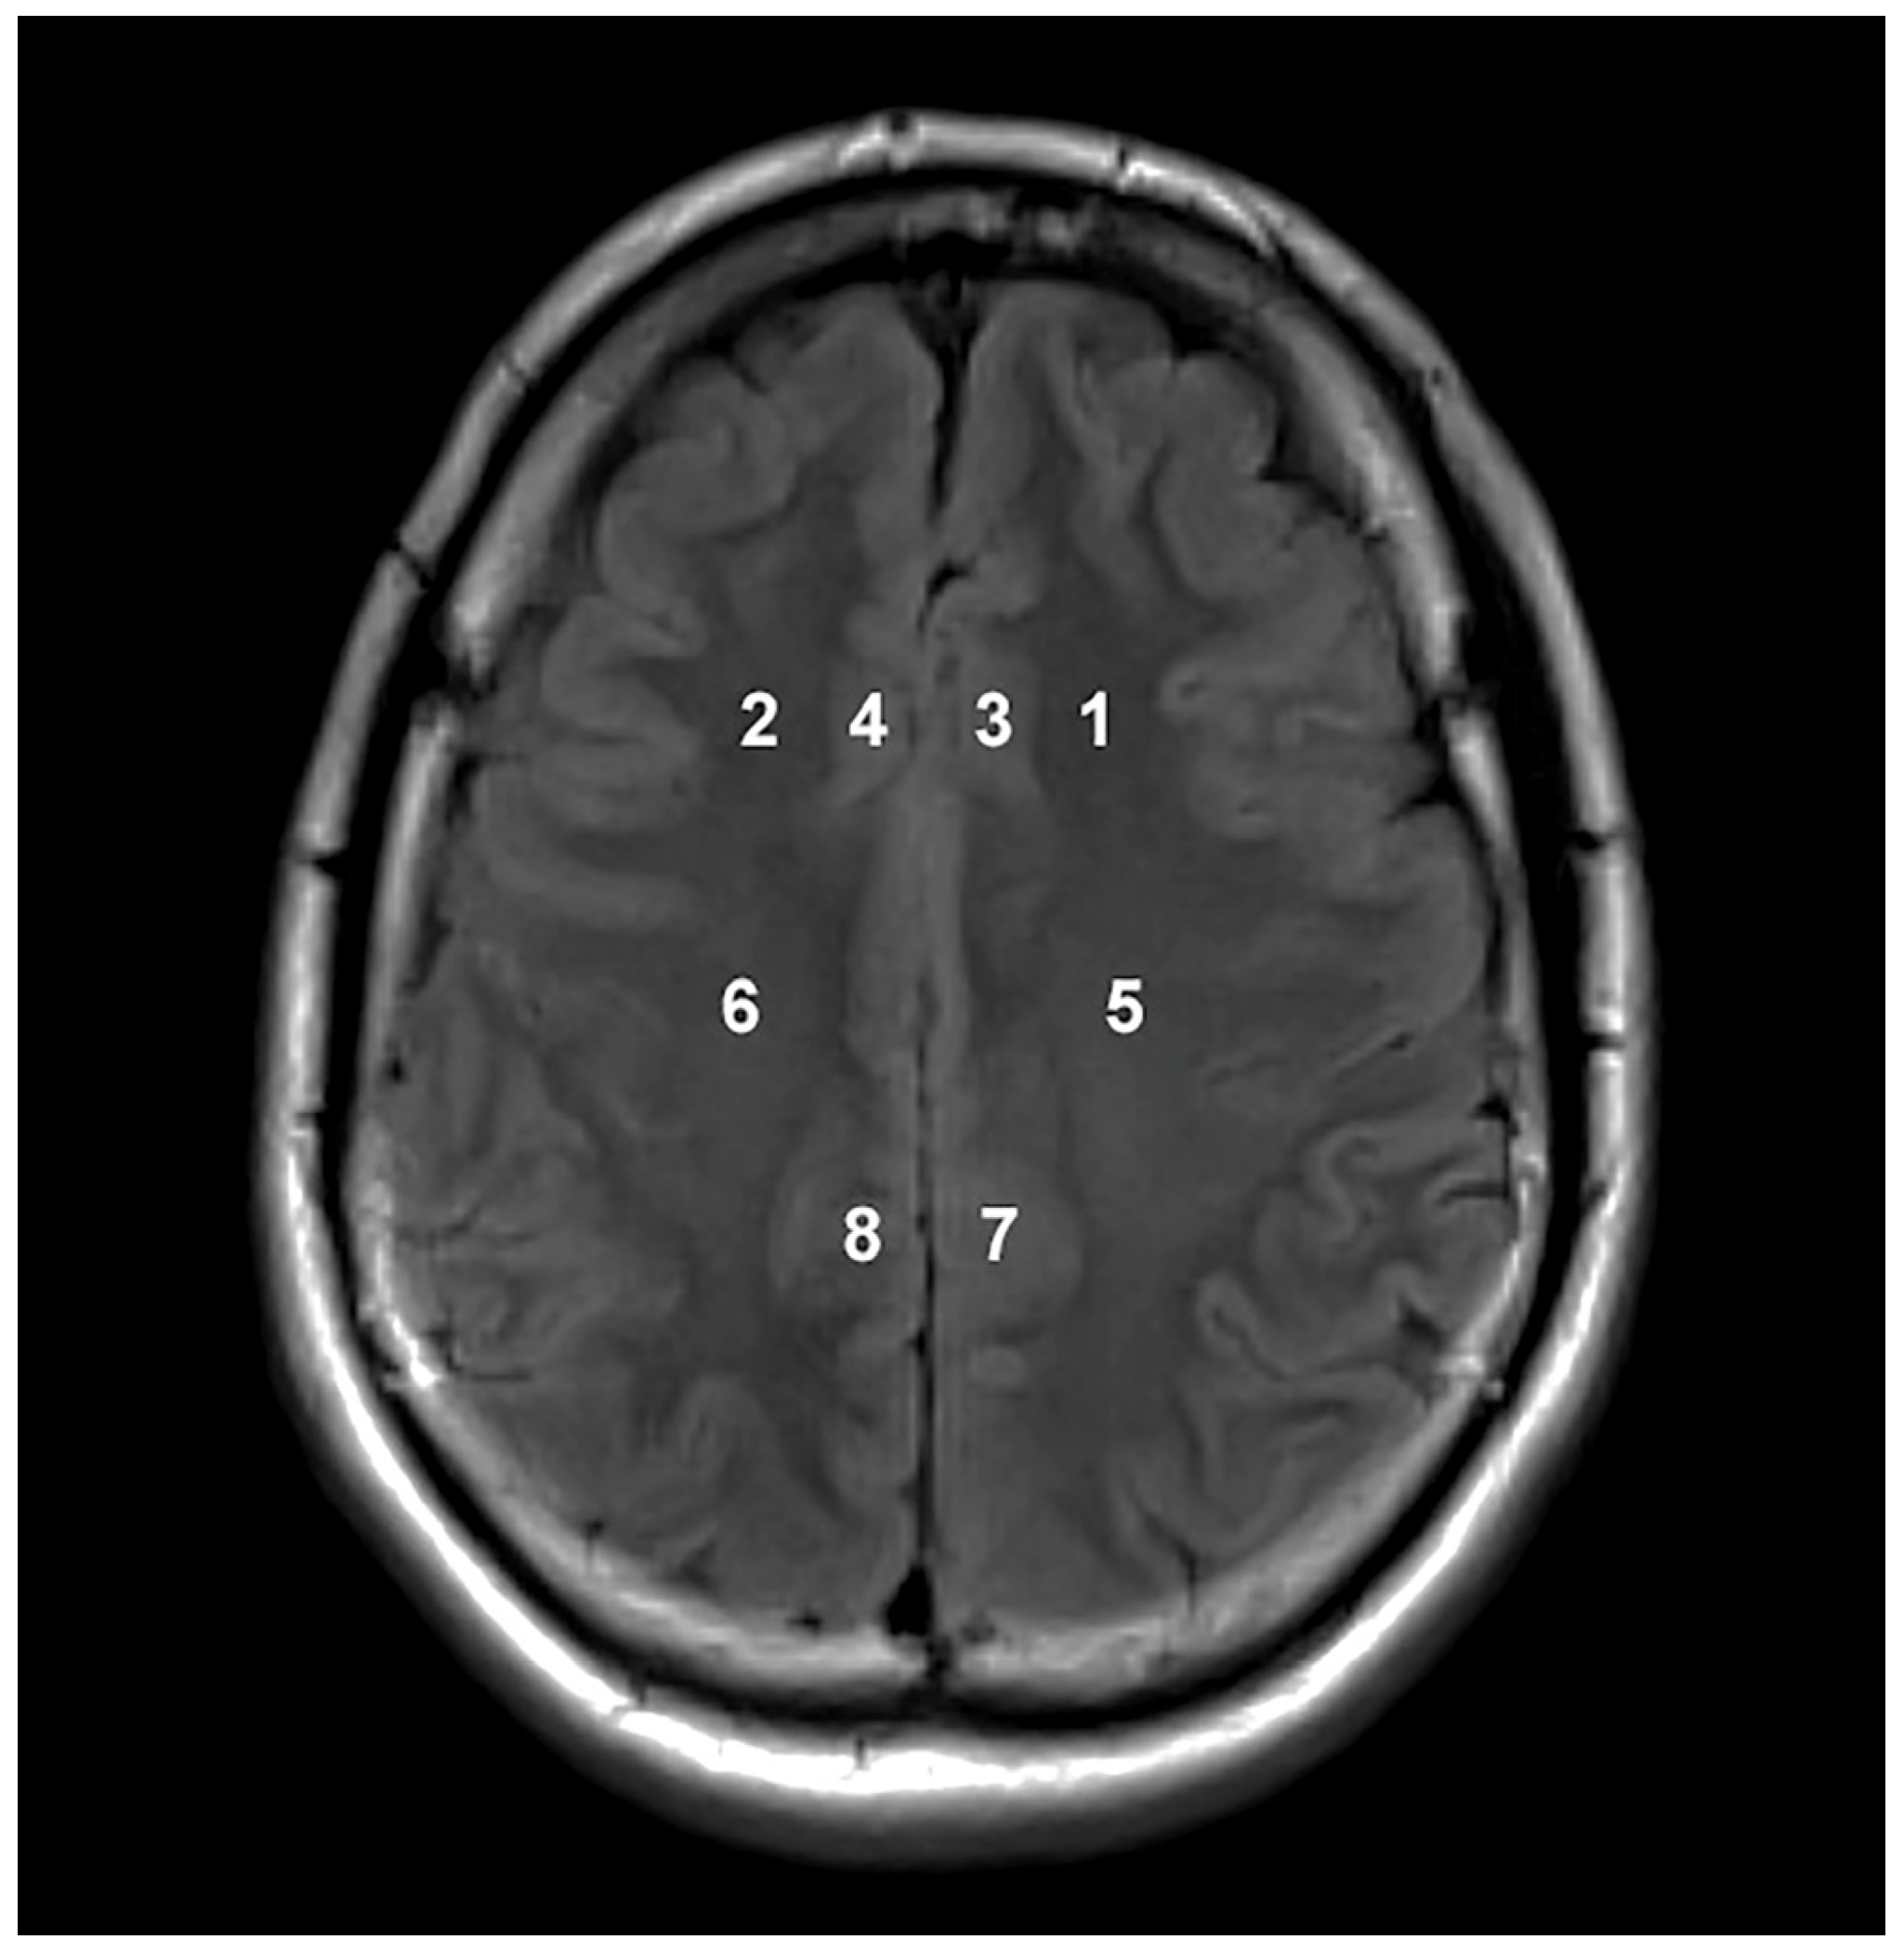

| Location | Metabolite Concentrations and Ratios | Groups Categorized According to Disease Severity | Contribution % | ||

|---|---|---|---|---|---|

| Mild | Moderate | Severe | |||

| 1 | Cr | 6.469 *2 | 5.827 *1 | 5.233 | 50.333 |

| NAA | 9.535 *2 | 8.902 *1 | 8.291 | 29.333 | |

| Cho/NAA | 0.666 | 0.701 | 0.739 *1 | 8.000 | |

| 2 | Cr | 6.517 *2 | 5.973 *1 | 5.321 | 37.652 |

| NAA | 10.075 *2 | 9.384 *1 | 8.502 | 28.340 | |

| Cho/Cr | 1.181 | 1.284 *1 | 1.390 *2 | 17.814 | |

| 3 | Cho | 1.783 *1 | 1.651 | 1.550 | 42.105 |

| Cho/NAA | 0.756 | 0.801 | 0.846 *1 | 24.342 | |

| Cr | 6.743 *2 | 5.891 *1 | 5.133 | 11.842 | |

| 4 | Cho/NAA | 0.760 | 0.784 | 0.839 *1 | 38.767 |

| Cr | 6.910 *2 | 5.833 *1 | 5.274 | 26.872 | |

| NAA | 7.700 *2 | 6.716 *1 | 6.099 | 14.978 | |

| 5 | Cho/NAA | 0.534 | 0.571 | 0.599 *1 | 22.131 |

| NAA | 12.075 *2 | 10.631 *1 | 9.671 | 20.765 | |

| Cr | 6.028 *2 | 5.482 *1 | 4.894 | 18.852 | |

| 6 | Cr | 6.398 *2 | 5.822 *1 | 5.133 | 36.842 |

| NAA | 12.848 *2 | 11.631 *1 | 10.054 | 22.601 | |

| Cho | 2.082 *1 | 1.979 *1 | 1.773 | 18.576 | |

| 7 | Cr | 7.199 *2 | 7.054 *1 | 6.141 | 42.246 |

| Cho | 2.033 | 2.051 | 1.982 | 26.738 | |

| NAA | 11.706 *1 | 10.895 *1 | 9.303 | 14.973 | |

| 8 | Cr | 7.248 *2 | 6.600 *1 | 6.017 | 35.821 |

| Cho | 2.069 | 2.055 | 1.887 | 32.537 | |

| NAA | 11.411 *1 | 10.454 *1 | 8.920 | 21.493 | |